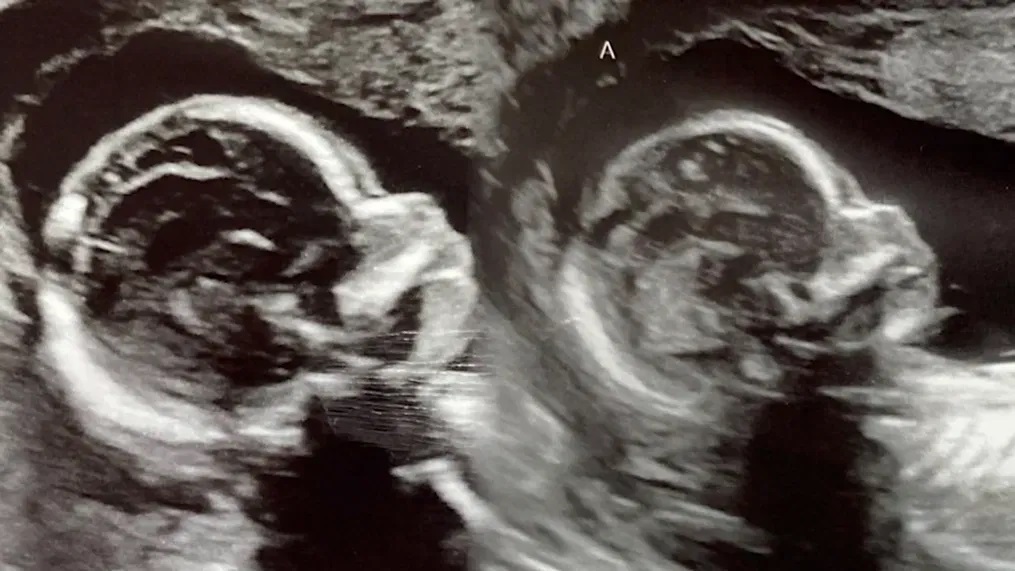

أصبحت امرأة من ولاية ألاباما الاميركية وُلدت برحمين، حاملاً بتوأم ينموّ كل منهما في رحم.

وخلال فحص روتيني بالموجات فوق الصوتية في مايو الفائت، علمت هاتشر، وهي أم لثلاثة أبناء، أنها حامل بتوأم وأنّ كل جنين منهما ينمو في أحد رحميها.

ويُعدّ الحمل في كل من الرحمين نادر الحدوث. وقالت هاتشر إن الأطباء أعلموها أنّ احتمال حصول حمل مماثل هو واحد على خمسة ملايين.